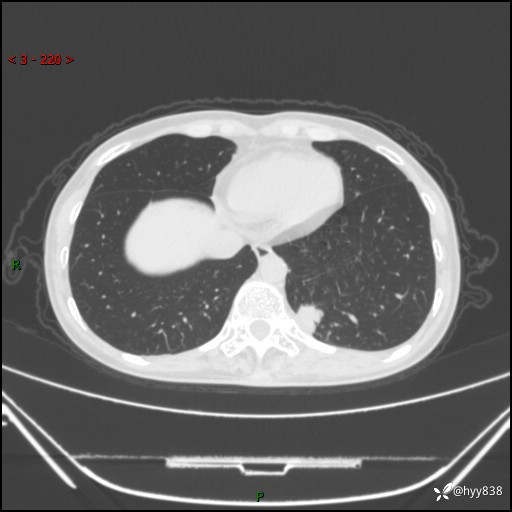

胸部CT平扫

增强动脉期+静脉期

各期CT值:48hu 65hu 76hu